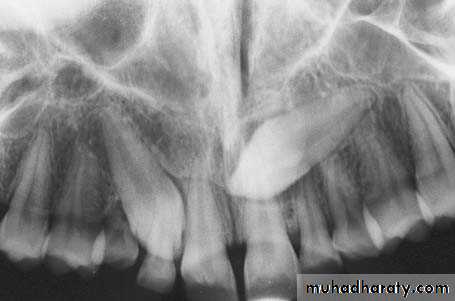

Radiograph showing impacted maxillary canines. Right canine is located labially while left canine is located palatally

Radiograph showing impacted maxillary canines with a palatal localization